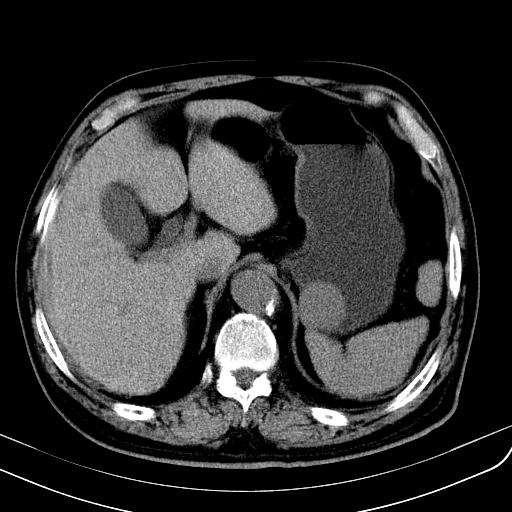

胃底靠近胃大弯处可见一圆形软组织影,直径为3.45cm,ct值约为30.1hu

胃底间质瘤

胃底平滑肌瘤

考虑为胃底间质瘤

边缘光滑,密度均匀,良性占位,首先考虑平滑肌瘤。

边缘光滑,密度均匀,良性占位,首先考虑平滑肌瘤。其实平滑肌瘤也是间质瘤的一种